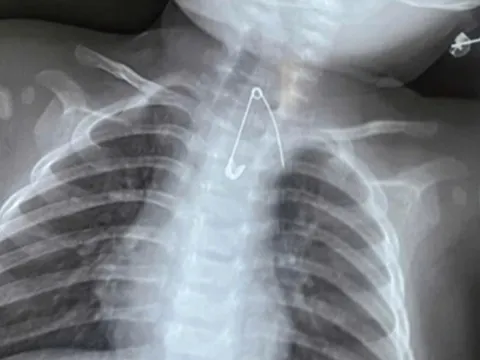

Đau bụng đi khám, người đàn ông "sốc" phát hiện bàn chải nằm trong bụng 52 năm

Nuốt phải bàn chải từ năm 12 tuổi nhưng giấu gia đình vì sợ bị mắng, nhầm tưởng vật thể sẽ tự phân hủy theo thời gian nhưng không ngờ đên khi 64 tuổi người đàn ông "sốc" khi biết dị vật vẫn nguyên vẹn trong bụng.